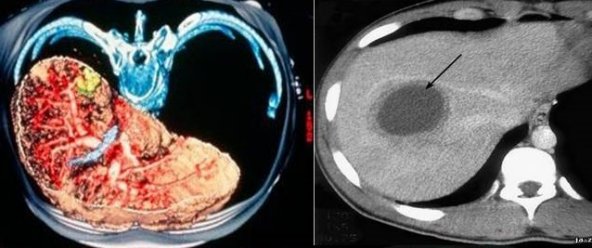

Методы динамического контрастирования печени на МРТ

Раздел: Снимки-подсказки